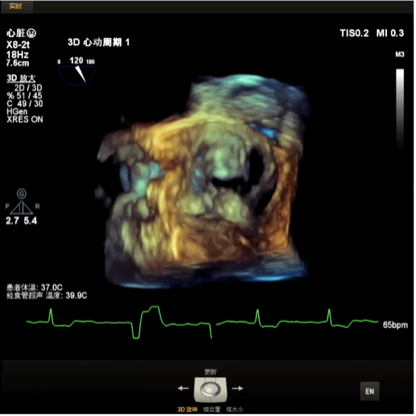

该病例为70岁女性患者,间歇胸闷气短17年,反复住院药物保守治疗,效果不佳,10日前症状加重,伴有胸痛、头晕、黑朦,双下肢水肿,转于我院就诊。经检查分析,诊断为重度主动脉瓣狭窄,风心病,患者主动脉瓣叶增厚,左心耳血栓,左冠开口小于10mm,存在一定冠脉阻塞风险,右侧股动脉分叉在股骨头中点,左侧股动脉分叉高于股骨头中点,双侧髂外动脉最小直径小于5.5mm,主动脉弓角偏大,对血管介入造成难点,同时易引起血管并发症,手术难度大。经杨毅宁教授团队充分评估,对患者采取全麻下经食道超声监测,选用目前行业最低入路要求美敦力递送系统配合自带内联鞘进行介入。

主动脉瓣狭窄(重度,跨瓣平均压差56mmHg),伴反流,主动脉瓣钙化,开放受限,有效开口面积0.6cm²;峰值流速4.56m/s,EF53%。经胸超声可见瓣膜开口严重受限,存在反流。